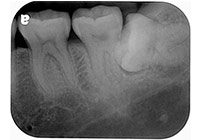

齒槽骨在牙齒拔除後的兩到三年,會面臨 40%-60%的萎縮,之後還會有每年 0.5%-1%後續的骨喪失,因此,一旦缺牙後若沒有儘快處理,患者日後將面臨齒槽骨萎縮引起的義齒製作困難及美觀問題。使用骨質增生膠原蛋白,來處理拔牙後的傷口。此材料適用的範圍不僅用於拔牙後傷口,所有顎骨中的病灶於手術後皆建議使用。牙科專用的3D電腦斷層攝影;與傳統醫療電腦斷層相比較,輻射劑量只有一般電腦斷層的1/50;切片厚度一般醫療電腦斷層是2.0公厘,牙科3D電腦斷層則只有0.1公厘,就診當天馬上拍攝電腦斷層,馬上獲得立體影像(圖01-04)

圖2